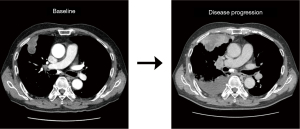

As the initial tumor tissue was intensely stained for MET, he was screened for a phase 2 trial of capmatinib (GEOMETRY mono-1, NCT02414139) as first-line treatment. Real-time polymerase chain reaction (RT-PCR) analysis for METex14 was negative, but MET GCN as determined by fluorescence in situ hybridization (FISH) was 13.5 indicating gene amplification. In addition, immunohistochemistry revealed MET overexpression (3+/3, >50%). Thus, he was enrolled in the trial and received capmatinib (400 mg, twice daily) as the first-line therapy. However, his disease progressed during capmatinib treatment. At the first response evaluation, which was performed after the initial 6 weeks of treatment, CT scans showed systemic progression of the disease including new metastatic lesions (Figure 1). We performed fluorescent in situ hybridization (FISH) for MET, and an amplicon-based next-generation sequencing (NGS, Illumina), with a panel consisting of 91 genes using the re-biopsied tumor samples from the liver. The NGS analysis revealed gene amplification of MYC (estimated copy number 5) and CEBPA without other nucleotide variants or fusion mutations, as well as MET amplification on FISH.